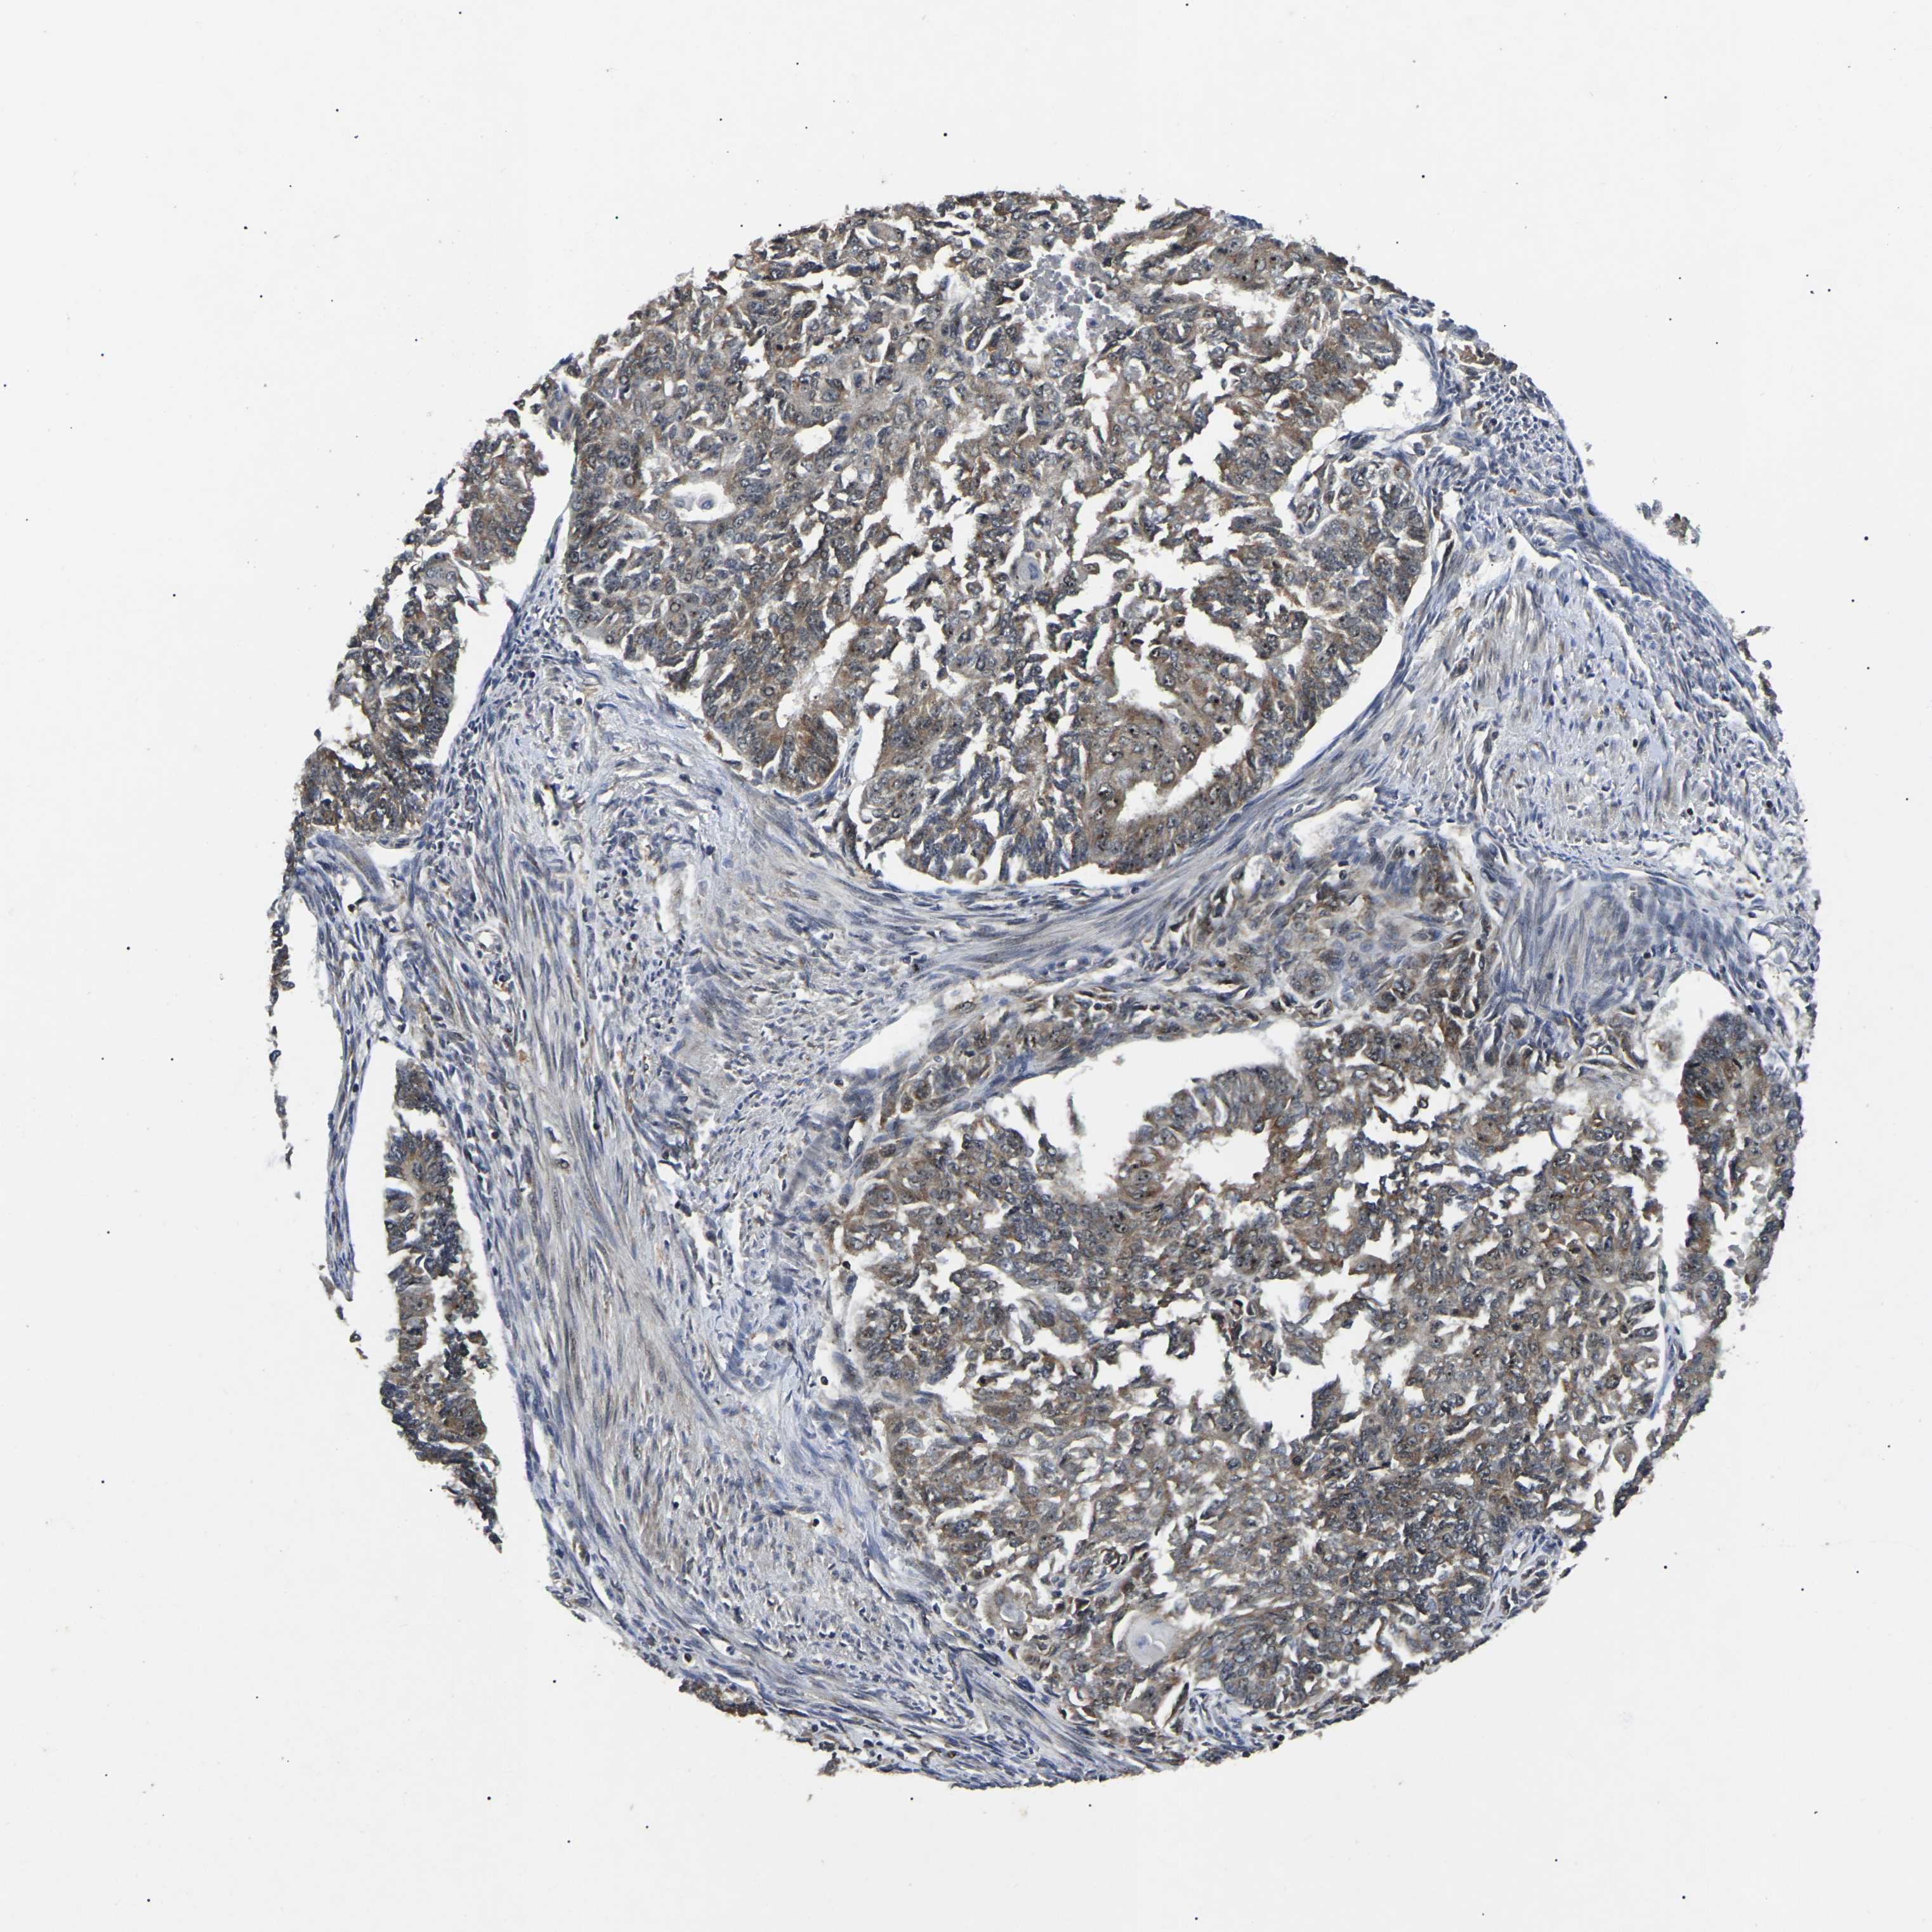

ENDOMETRIAL CANCER - Protein expressioni

A mouse-over function shows sample information and annotation data. Click on an image to view it in a full screen mode. Samples can be filtered based on level of antibody staining by selecting one or several of the following categories: high, medium, low and not detected. The assay and annotation is described here.

Note that samples used for immunohistochemistry by the Human Protein Atlas do not correspond to samples in the TCGA dataset.

Antibody stainingi

Antibody staining in the annotated cell types in the current human tissue is reported as not detected, low, medium, or high, based on conventional immunohistochemistry profiling in selected tissues. This score is based on the combination of the staining intensity and fraction of stained cells.

Each image is clickable and will lead to virtual microscopy that enables deeper exploration of all samples and also displays staining intensity scores, fraction scores and subcellular localization as well as patient and tissue information for each sample.

Antibody HPA019058

Antibody HPA026672

Staining

High

Medium

Low

Not detected

Intensity

Strong

Moderate

Weak

Negative

Quantity

>75%

75%-25%

<25%

None

Location

Nuclear

Cytoplasmic/membranous

Cytoplasmic/membranous,nuclear

Adenocarcinoma, NOS